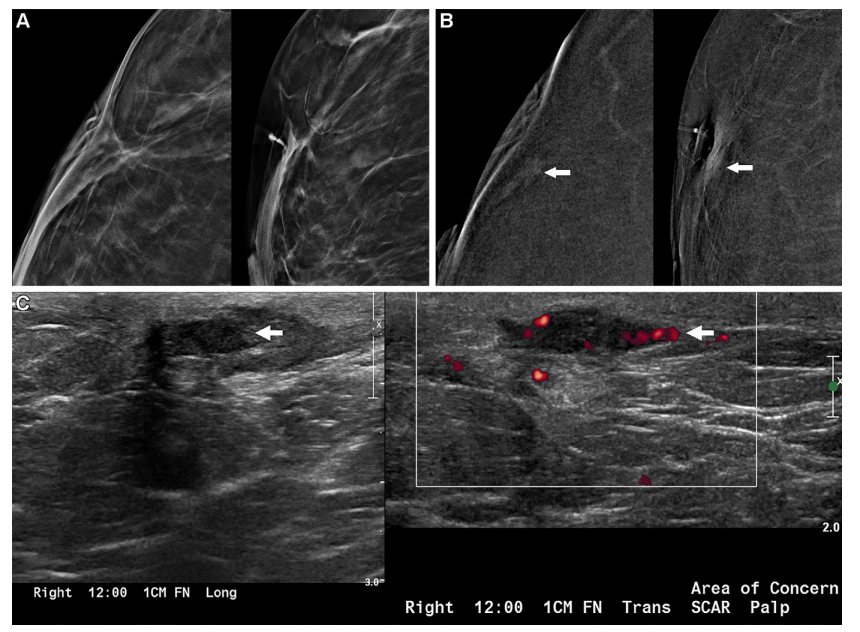

Figure 4: Images in a 47-year-old woman with recurrent invasive lobular carcinoma (ILC) at the scar detected clinically 6 months after imaging (interval cancer). (A)* Close-up craniocaudal (CC) (left) and mediolateral oblique (MLO) (right) digital breast tomosynthesis 6-mm slab images of the right breast show the area of scarring from breast-conserving therapy 2 years earlier for multifocal estrogen receptor (ER)/progesterone receptor (PR)-positive, human epidermal growth factor receptor 2 (HER2) (ERBB2 gene)–positive ILC, interpreted as benign, Breast Imaging Reporting and Data System (BI-RADS) 2, by both observers. The participant completed both neoadjuvant and adjuvant chemotherapy and was taking tamoxifen. (B) Close-up CC (left) and MLO (right) recombined contrast-enhanced mammography (CEM) images show nonmass enhancement at the scar (arrows), interpreted as benign, BI-RADS 2, by both observers. (C) US scan in longitudinal plane (left) obtained 6 months later, when theparticipant reported feeling a lump at the scar, shows a superficial irregular, parallel, hypoechoic mass (arrow) at the scar; the mass shows internal vascularity on transverse power Doppler scan (right, arrow). US-guided core biopsy and mastectomy revealed a 2.4-cm grade 3 ILC, ER-positive, PR-negative, HER2-positive lesion (Ki-67 proliferation index of 90%), with one of two sentinel nodes showing isolated tumor cells (N0).

图4: 一位47岁女性在疤痕处临床发现复发性浸润性小叶癌(ILC),影像检查后6个月(间隔癌)。(A) 近距离头尾位(CC)(左)和内外侧斜位(MLO)(右)数字乳腺断层合成的6毫米薄片图像显示右乳房在2年前因多灶性雌激素受体(ER)/孕激素受体(PR)阳性、人表皮生长因子受体2(HER2)(ERBB2基因)阳性ILC接受乳房保留治疗后的疤痕区,两个观察者均解释为良性(乳腺影像报告和数据系统BI-RADS 2)。参与者完成了新辅助和辅助化疗,并服用他莫昔芬。(B) 近距离CC(左)和MLO(右)重组的对比增强乳腺摄影(CEM)图像显示疤痕处的非肿块增强(箭头),两个观察者均解释为良性(BI-RADS 2)。(C) 6个月后,当参与者报告在疤痕处感觉到一个肿块时,获得的纵向平面超声扫描(左)显示疤痕处有一个表浅的不规则、平行、低回声的肿块(箭头);横向功率多普勒扫描(右,箭头)显示肿块内部有血管。超声引导的核心活检和乳房切除术显示一个2.4厘米的3级ILC,ER阳性,PR阴性,HER2阳性病变(Ki-67增殖指数为90%),两个前哨淋巴结中的一个显示孤立的肿瘤细胞(N0)。